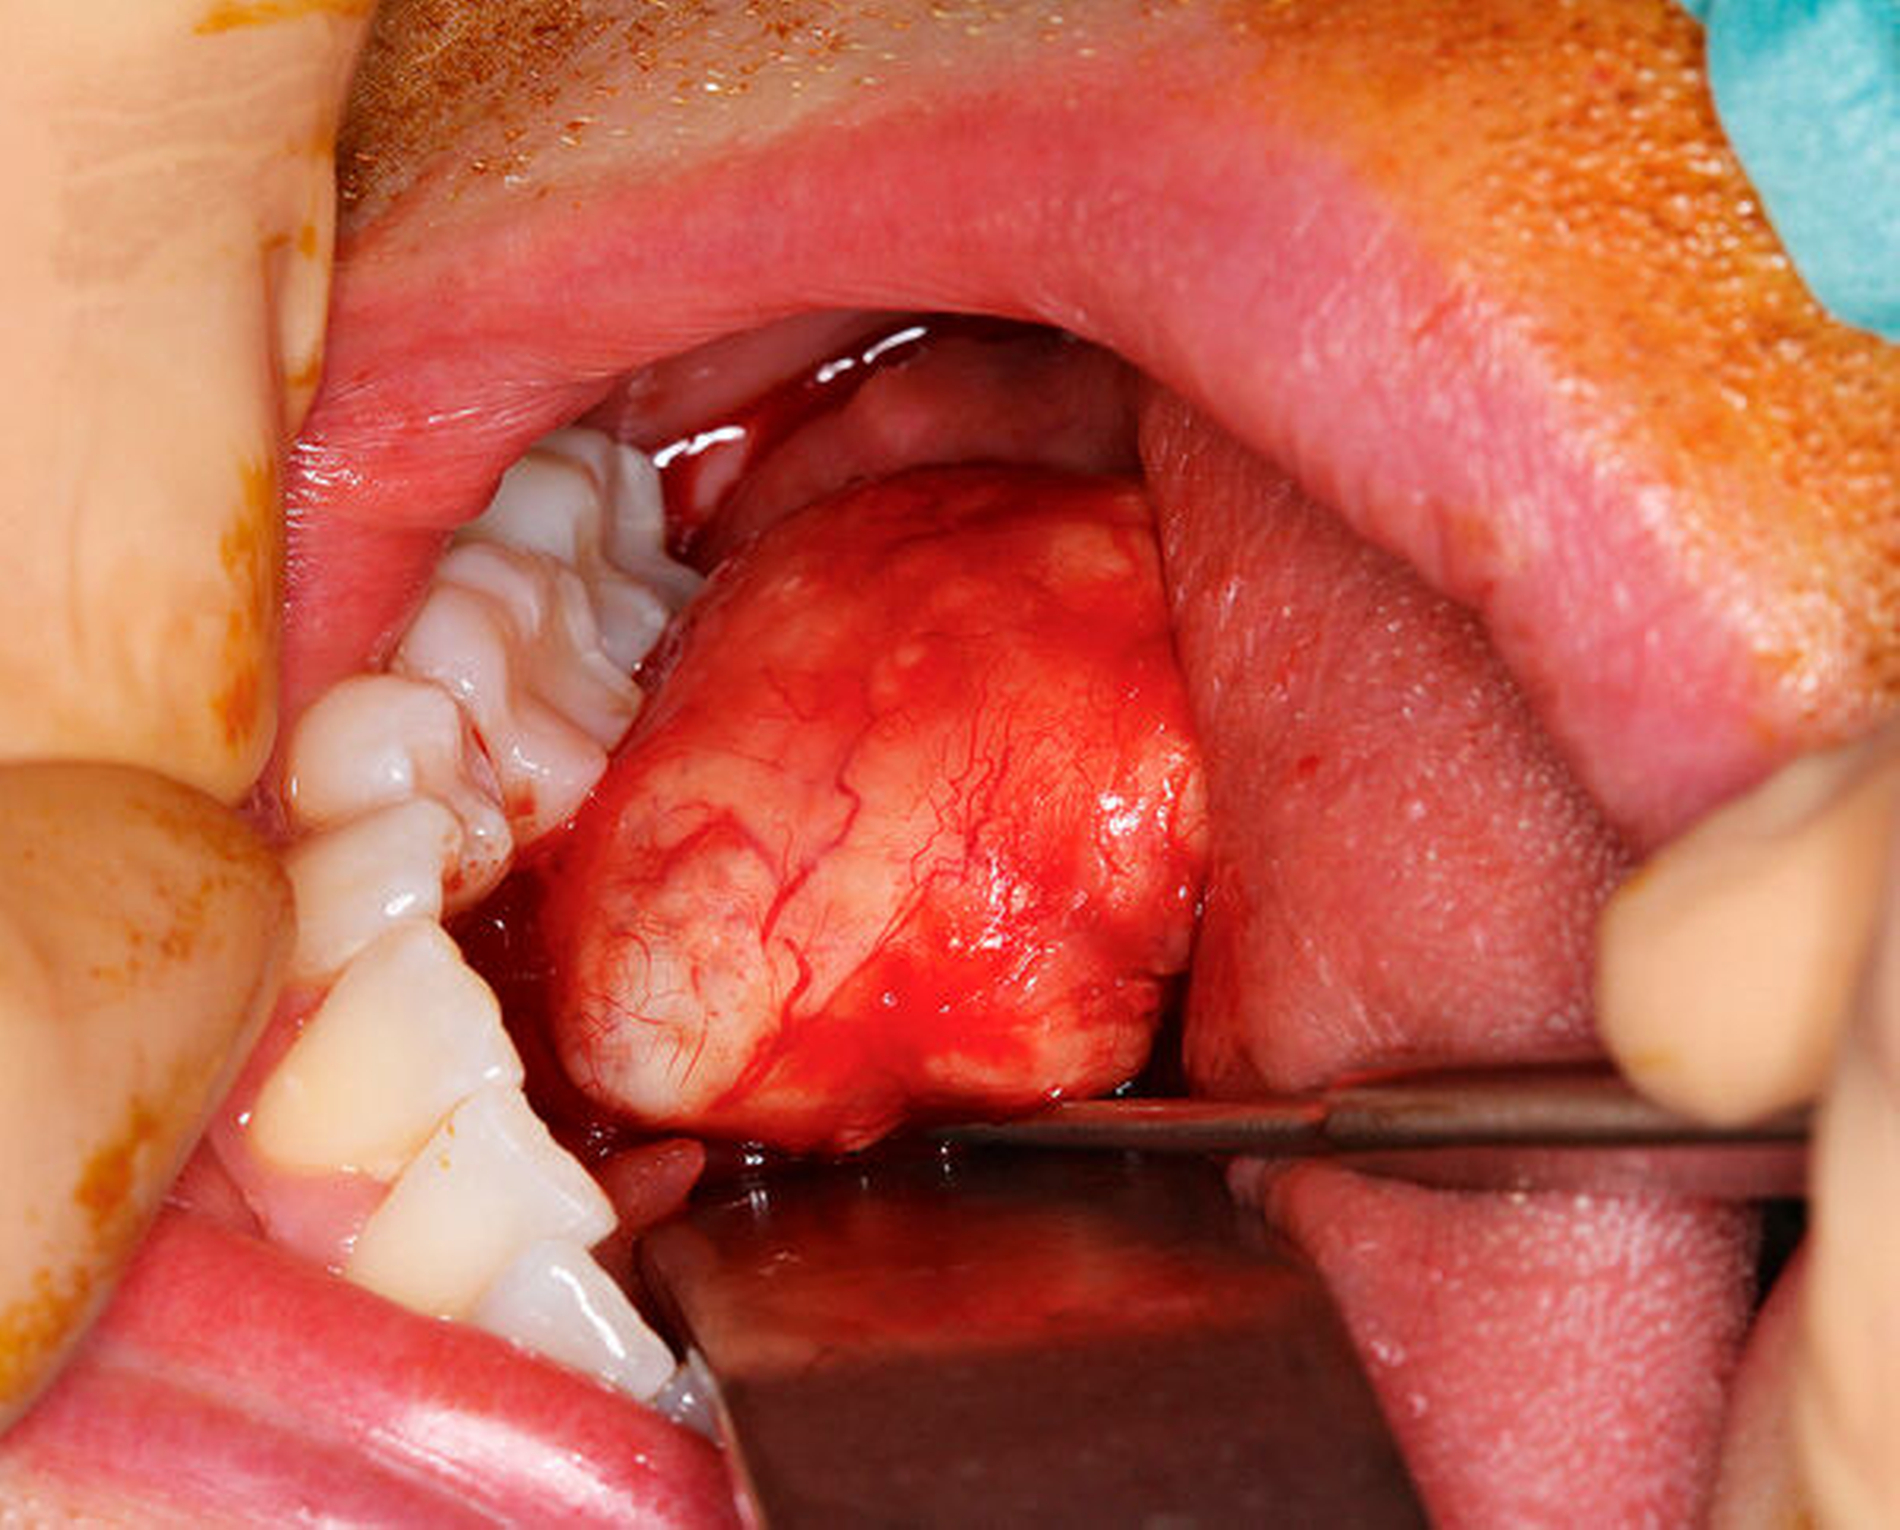

Zur Diagnosesicherung und Therapie des Befunds erfolgte die vollständige Exstirpation der Raumforderung über einen Zugang im Bereich des Mundbodens rechts (Abbildungen 3 und 4). Zusätzlich erfolgte die Extraktion des Zahns 36. Die Untersuchung des Gewebes zeigte das histopathologische Bild eines pseudogekapselten Tumors aus myxoidem Bindegewebe mit Knorpelanteilen und mehreren epithelialen, benignen Proliferaten. Auf Basis des klinischen, des radiologischen und des histologischen Befunds ergab sich die Diagnose eines pleomorphen Adenoms.